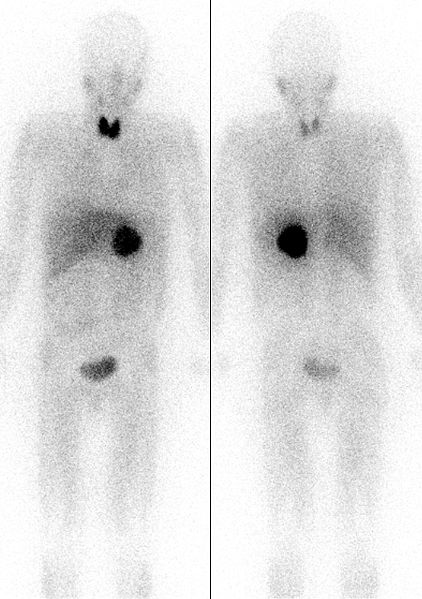

294. Drahreg01 Body scintographic image: pheochromocytoma. http://en.wikipedia.org/wiki/File:Pheochromocytoma_Scan.jpg .